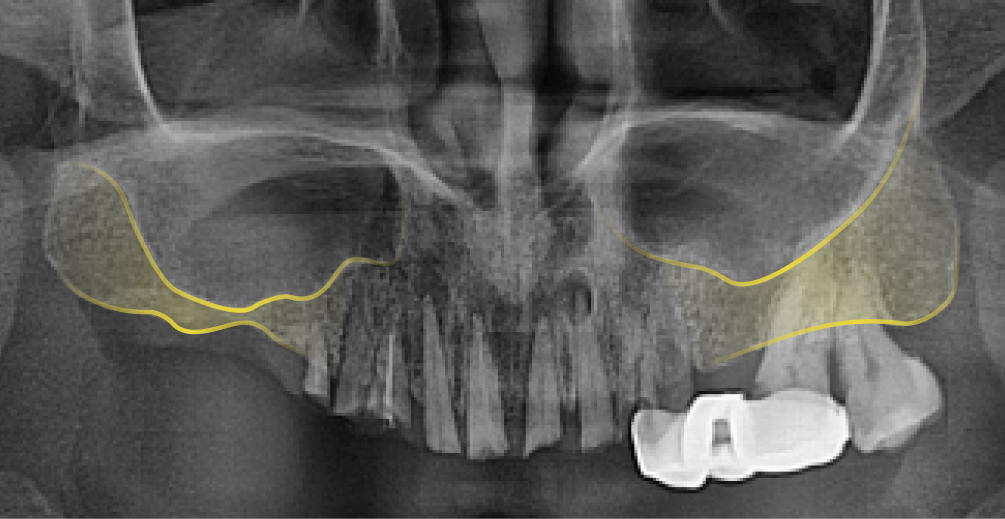

상악동(위턱뼈 속의 비어있는 공간)거상술은 상악동과 잇몸뼈 사이에 임플란트를 심을 수 있는 만큼의 충분한 뼈가 존재하지 않을 때, 그 공간을 살짝 들어 올려서 잇몸뼈를 채워 넣는 시술 을 말합니다.

상악동은 원래 팽창하려는 성질이 있어 치아가 빠진 이후 오랜 시간 방치했거나 나이가 들면서 치조골이 약해지면 상악동이 아래로 내려오면서 커지는 증상이 발생합니다. 이를 상악동의 함기화(Sinus Pneumatization) 라고 하며, 상악동이 아래로 내려오면서 임플란트 식립이 어려울 만큼 뼈가 얇아지게 됩니다. 이렇게 뼈가 얇아져 임플란트 식립이 어려울 때, 상악동을 위로 들어 올려 뼈를 이식하는 ‘상악동 거상술(Sinus Lift , Sinus Elevation)’을 진행합니다.

상악동은 아래턱에 비해 밀도가 낮고, 두껍지 않아서 찢어지거나 구멍이 생길 수 있는 위험이 있는 고난이도 수술이기 때문에 의료진의 경험과 시술 노하우, 그리고 안전한 장비를 갖춘 치과에서 시술받아야 합니다.